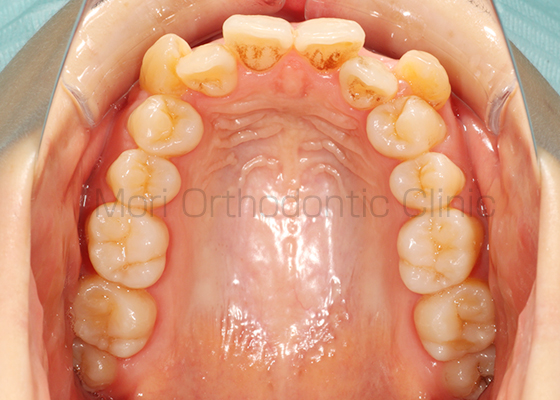

術前

術後

| 主訴 | 歯並び、八重歯 |

|---|---|

| 診断名 | AngleⅡ級叢生 |

| 年齢 | 30歳2か月 |

| 治療装置 | Multi-Bracket(表側矯正)、CARRIERE DISTALIZER |

| 抜歯部位 | 14,24,35,45 |

| 治療期間 | 2年1か月 |

| 治療費 | 825,120円(税込) |

| リスク・副作用 | 矯正治療による歯の移動に伴う痛み、歯根吸収、歯肉退縮、虫歯 |